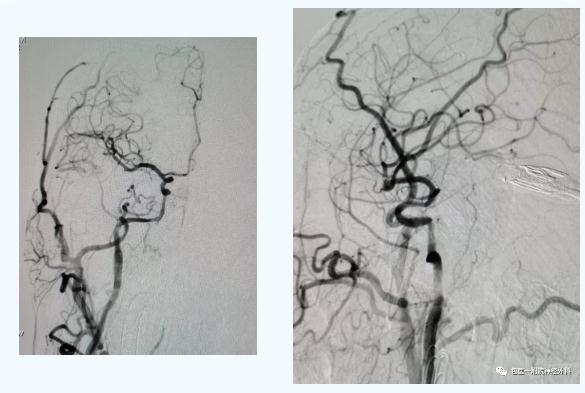

通过造影,发现张老伯远端血管存在狭窄与闭塞的情况,杨扬医生通过球囊、支架等介入器材为他成功开通右侧颈内动脉。

介入再通后造影